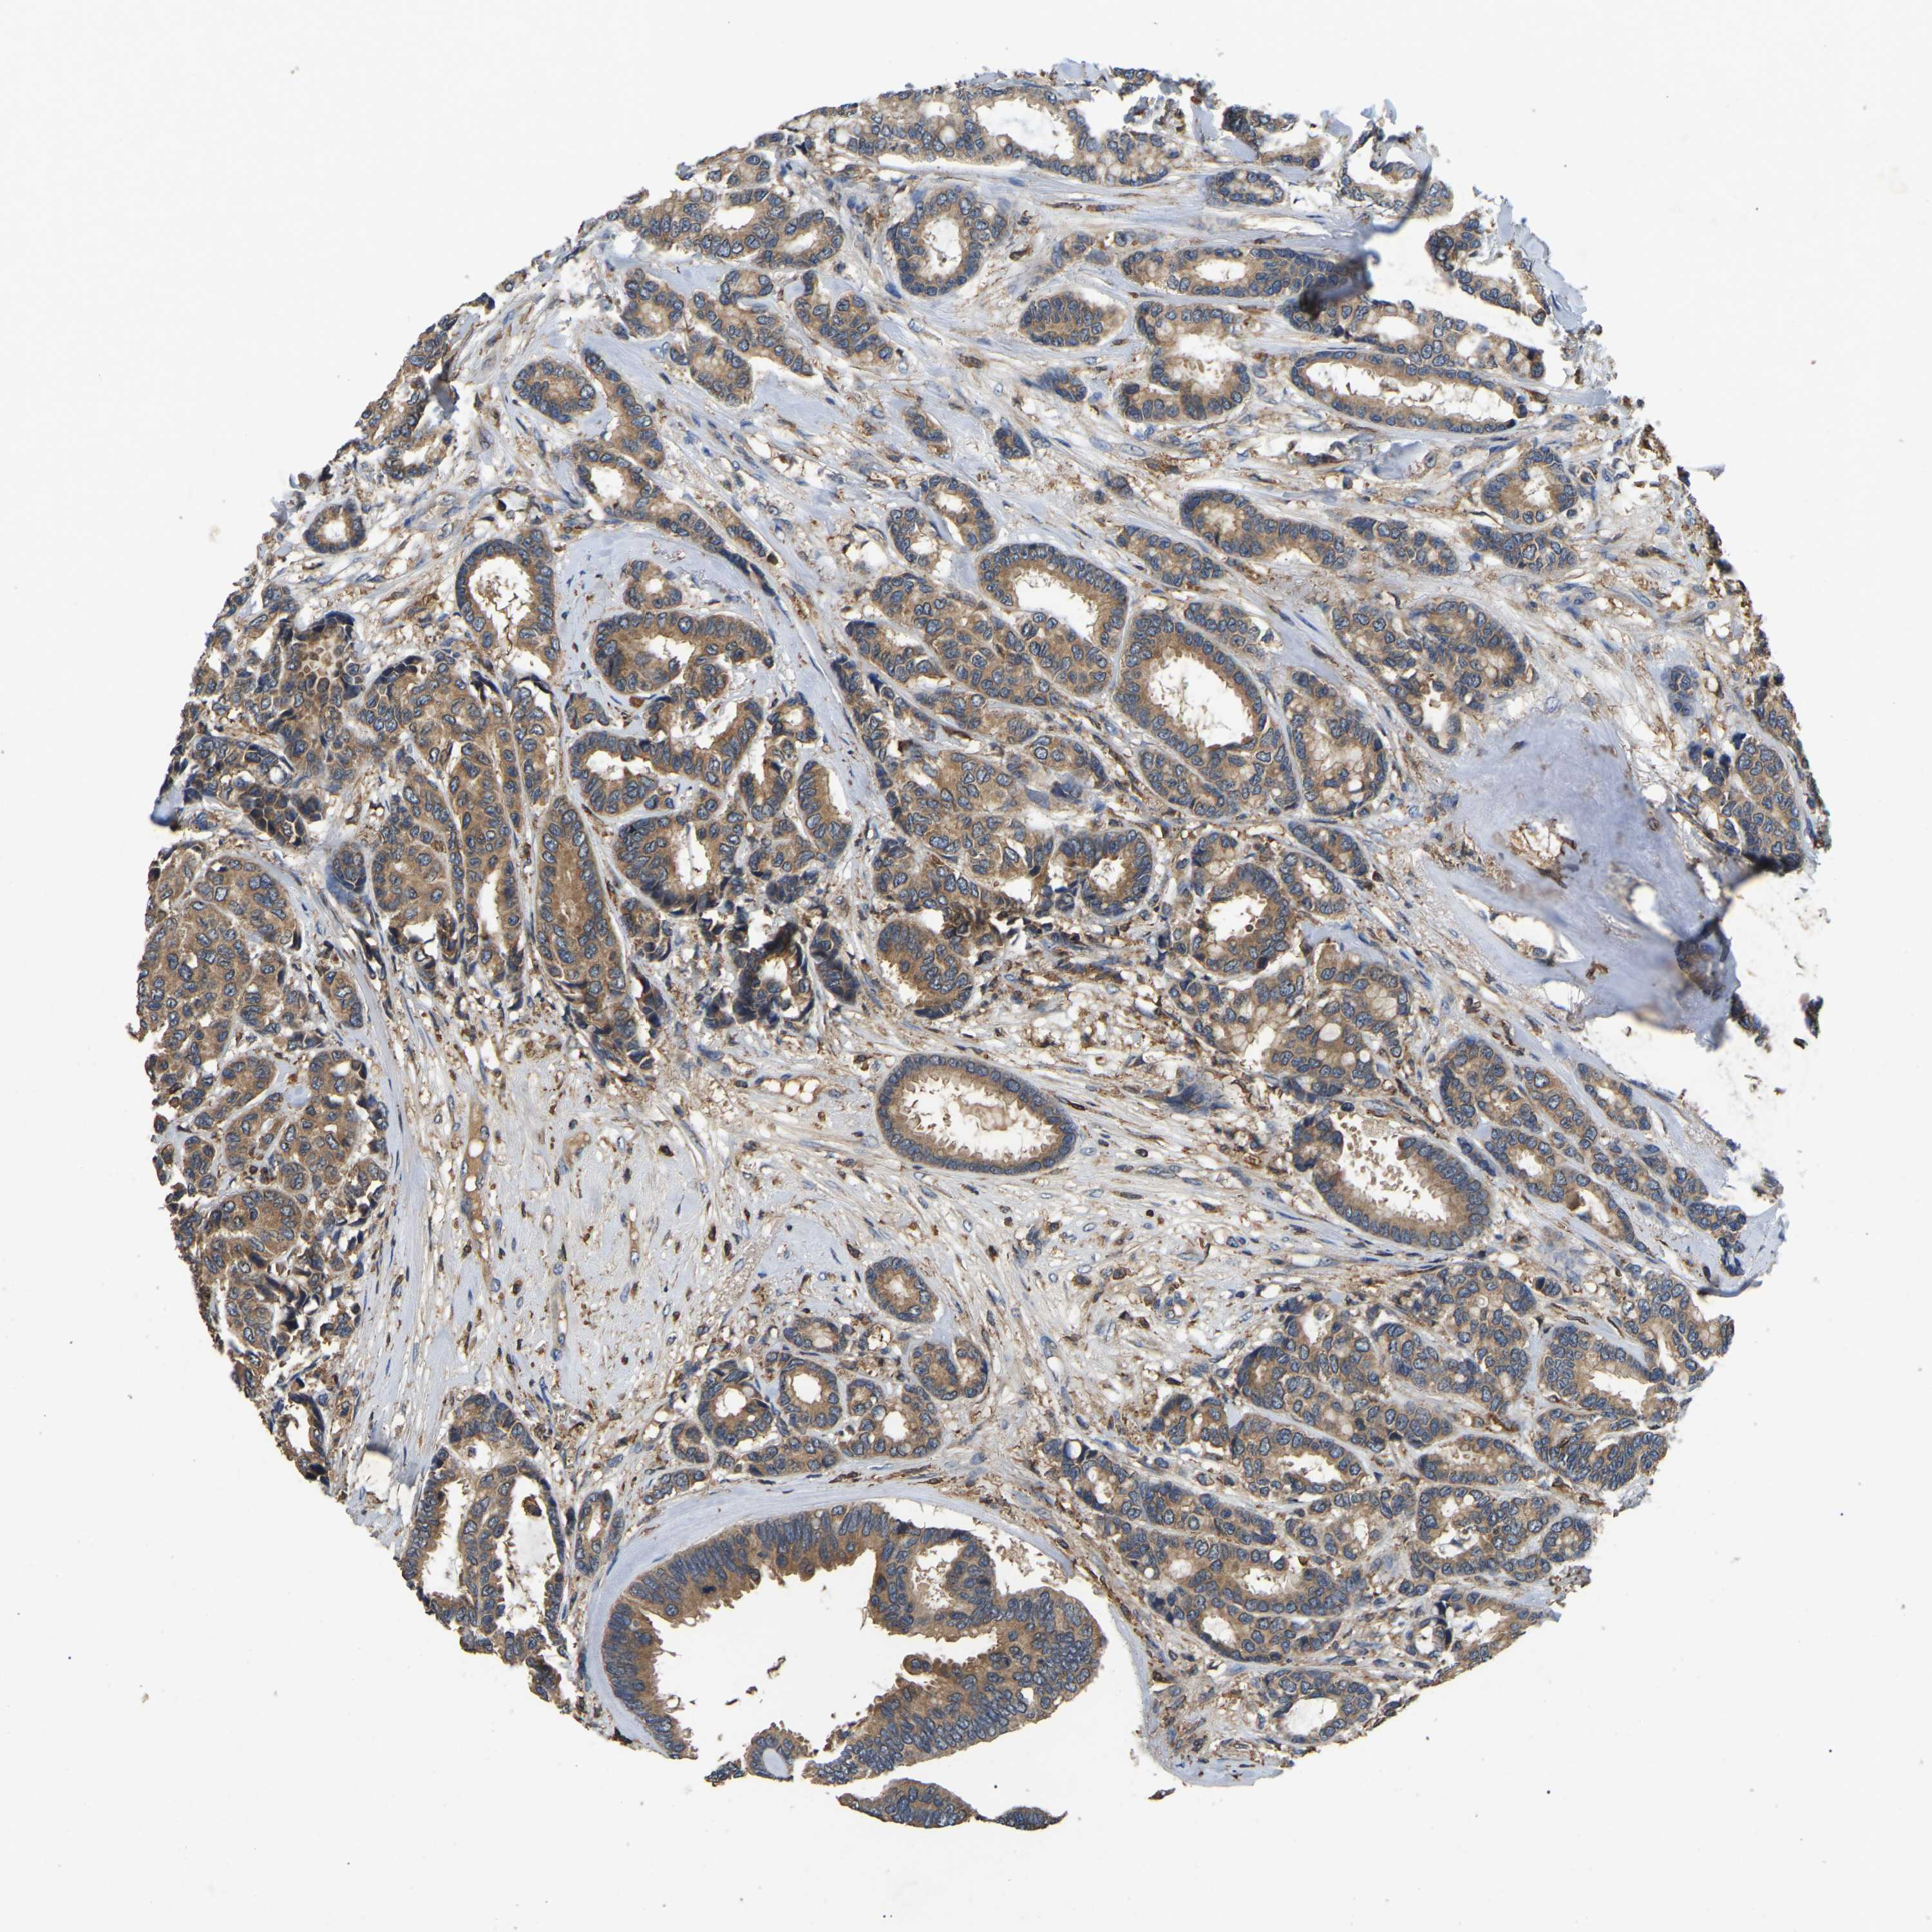

CANCER BREAST CANCER Show tissue menu

BRCA TCGA BRCA VALIDATION PROTEIN EXPRESSION